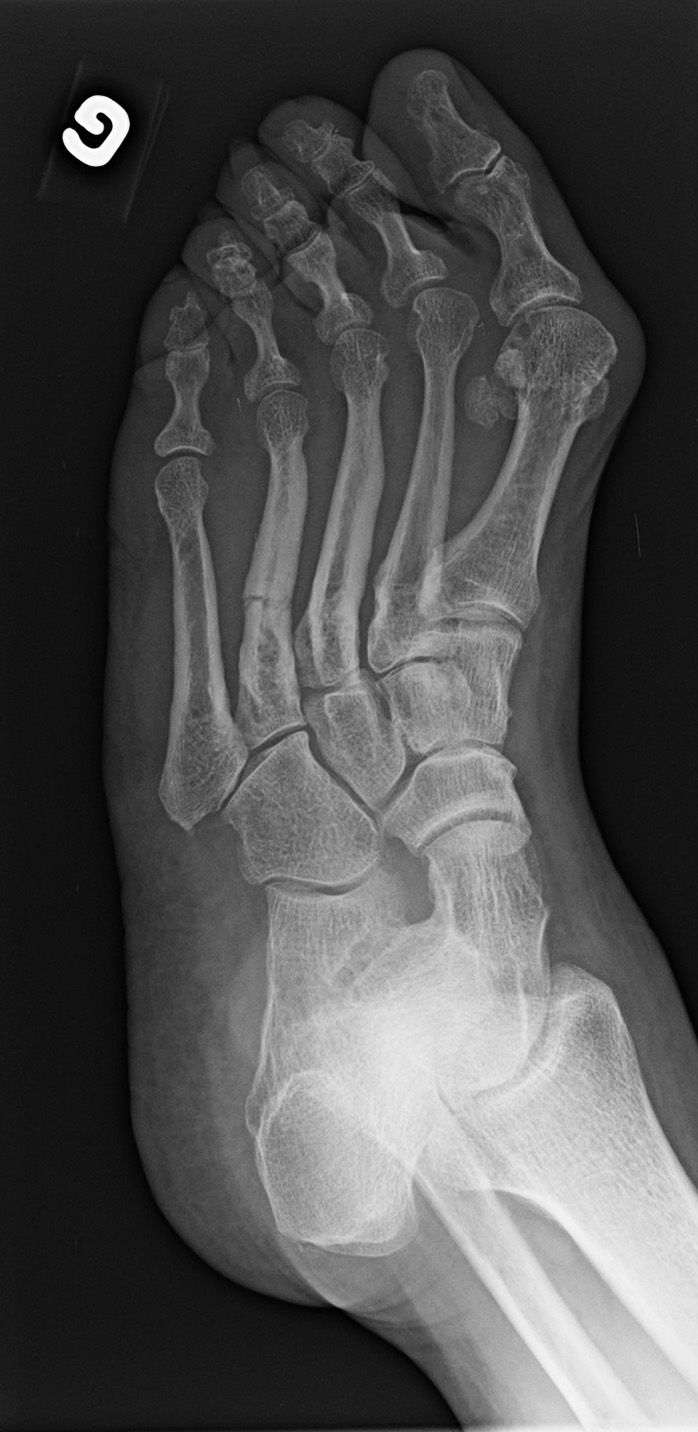

Metatarsal fracture (4th)

Linear hypodensity

4th metatarsal proximal third non-displaced fracture.

Callus

The fracture line is difficult to visualize and partially filled by a callus. This is a stress fracture of at least 10-14 days old.

Hallux valgus

Important hallux valgus with a metatarsophanlangeal angle increased to 40° (normal at 15°).

Metatarsus varus

The hallux valgus is associated to a metatarsus varus with an intermetatarsal angle increased to 15° (normal at 10°). This angle is underrated because of the abnormal forefoot structure (metatarsus adductus).

Interphalangeal angle

Normal interphalangeal angle of about 5° (this angle is considered normal if smaller than 8°).

Sesamoids

The sesamoids are displaced medially.